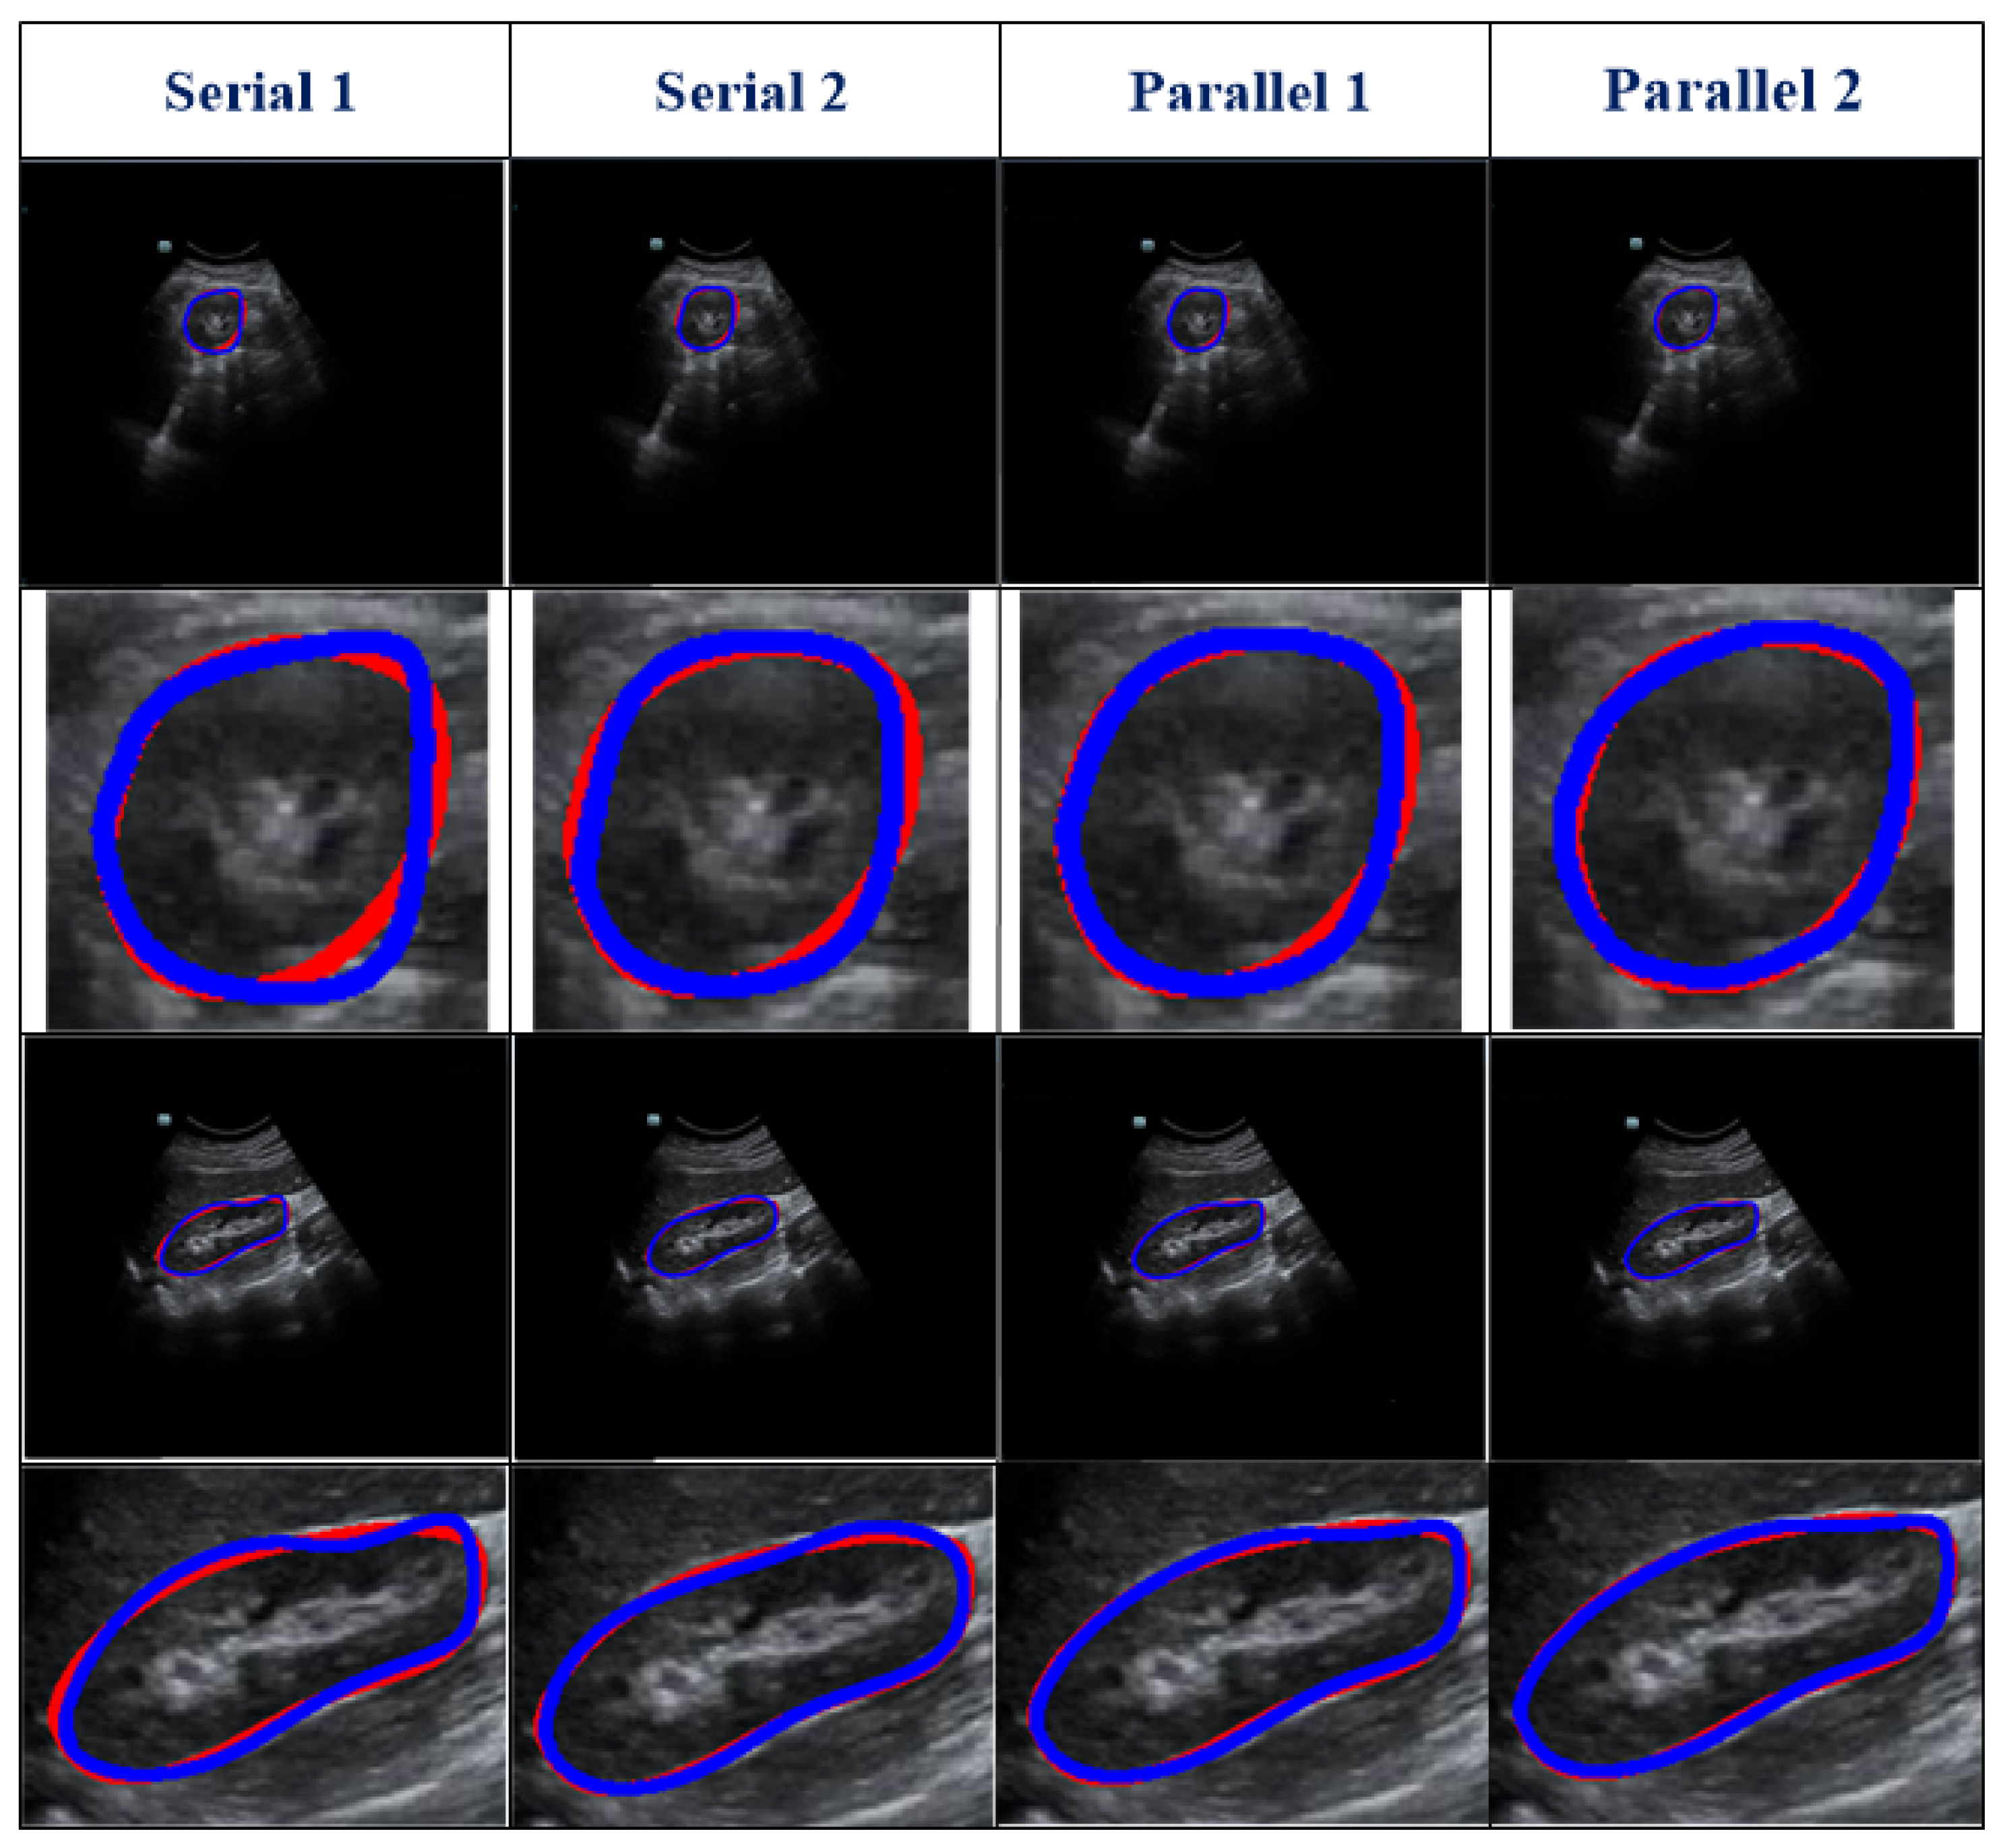

Table 2 represents the testing outcomes of four variant models based on the DSC value. Figure 5 represents the visual qualitative results of the four variant models based on two randomly selected cases. Parallel architectures (Parallel 1 and 2) showed better performance than serial architectures (Serial 1 and 2), with DSC and Ω values of 0.89 and 0.899 and 0.805 and 0.813, respectively, for the two parallel architectures. However, compared with Parallel 1, the DSC and Ω values of Parallel 2 increased by 1.01% and 0.99%, respectively. Hence, we used Parallel 2 as the coarse segmentation step of our proposed method.

Differences among different models. Serials 1 and 2 use serial architecture of AG followed by SE and SE followed by AG, respectively. Parallel 1 and 2 denote parallel architecture, using features from the decoding and encoding paths, respectively, as the input for the SE. The details of the four models are shown in Figure 3.

Figure 5.

Visual results of four variant models. Two randomly selected cases are presented under different views. The blue and red lines show the experimental outcome and GT, respectively. The first two rows show the axial view, and the last two rows show the sagittal view. The first and third rows show the overlap between the segmentation result and the GT. The second and fourth rows show the corresponding zoomed-in display.

As shown in Table 2, different serial and parallel architectures resulted in different levels of performance for the coarse segmentation strategy. There are three aspects of the outcomes presented in Table 2 to be discussed. First, overall, the parallel architecture showed better capability than the serial architecture. Both the AG [18] and SE [19] modules are known to have a good ability to boost relevant features and remove irrelevant features. However, using serial AG and SE modules may cause the deletion of a large amount of information, some of which may be useful. Second, of the serial architectures evaluated, SE-AG (Figure 3b) showed better performance than AG-SE (Figure 3a). The main reason for this is that the AG module has a more complex structure than the SE module (as shown in Section 2.3), which makes it difficult to train the AG module and avoid the loss of meaningful information. Third, as illustrated in Table 2, the Parallel 2 model performed better than the Parallel 1 model. The main difference between these two parallel architectures is in the input for the SE module, with one using features from the decoding path (Parallel 1) and the other using features from the encoding path (Parallel 2). Parallel 2 may perform better because using encoding features as the input for the SE module carries the merit of the SE module to emphasize meaningful features and suppress less useful features.